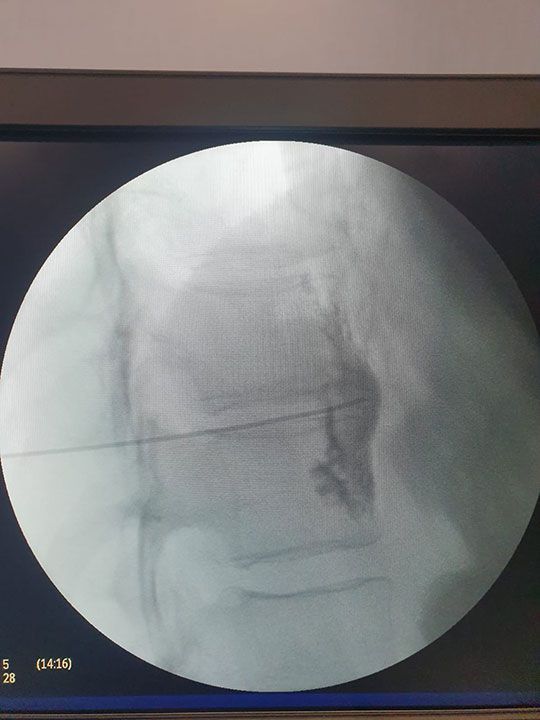

Cervicalgia (Dolor del Cuello)

Puede ser una fuente de molestias persistentes y limitaciones en la movilidad, brindamos variedad de opciones de tratamiento que van desde terapias conservadoras con apoyo de médicos especialistas hasta procedimientos intervencionistas guiados por imágenes, diseñados para aliviar el dolor cervical y restaurar la funcionalidad del cuello, permitiendo a los pacientes volver a disfrutar de una vida activa y sin dolor.